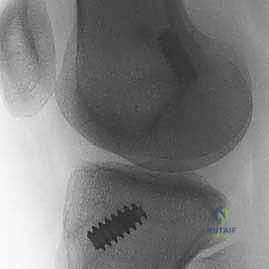

- الأشعة السينية (X-rays): تُطلب أولاً لنفي وجود أي كسور عظمية مصاحبة، مثل كسر "سيجوند" (Segond Fracture) وهو كسر قلعي صغير في الجانب الخارجي للقصبة يُعتبر علامة شبه مؤكدة لتمزق الرباط الصليبي.

- الطعم الذاتي من الوتر الرضفي (Bone-Patellar Tendon-Bone - BPTB):

- يتم أخذ الثلث الأوسط من الوتر الذي يربط صابونة الركبة بالقصبة، مع كتلة عظمية صغيرة من كلا الطرفين.

- المميزات: التئام عظم-إلى-عظم سريع وقوي جداً. يعتبر "المعيار الذهبي" للرياضيين المحترفين في رياضات الالتحام.

- العيوب: ألم في مقدمة الركبة عند الركوع، خطر بسيط للإصابة بكسر في الصابونة.